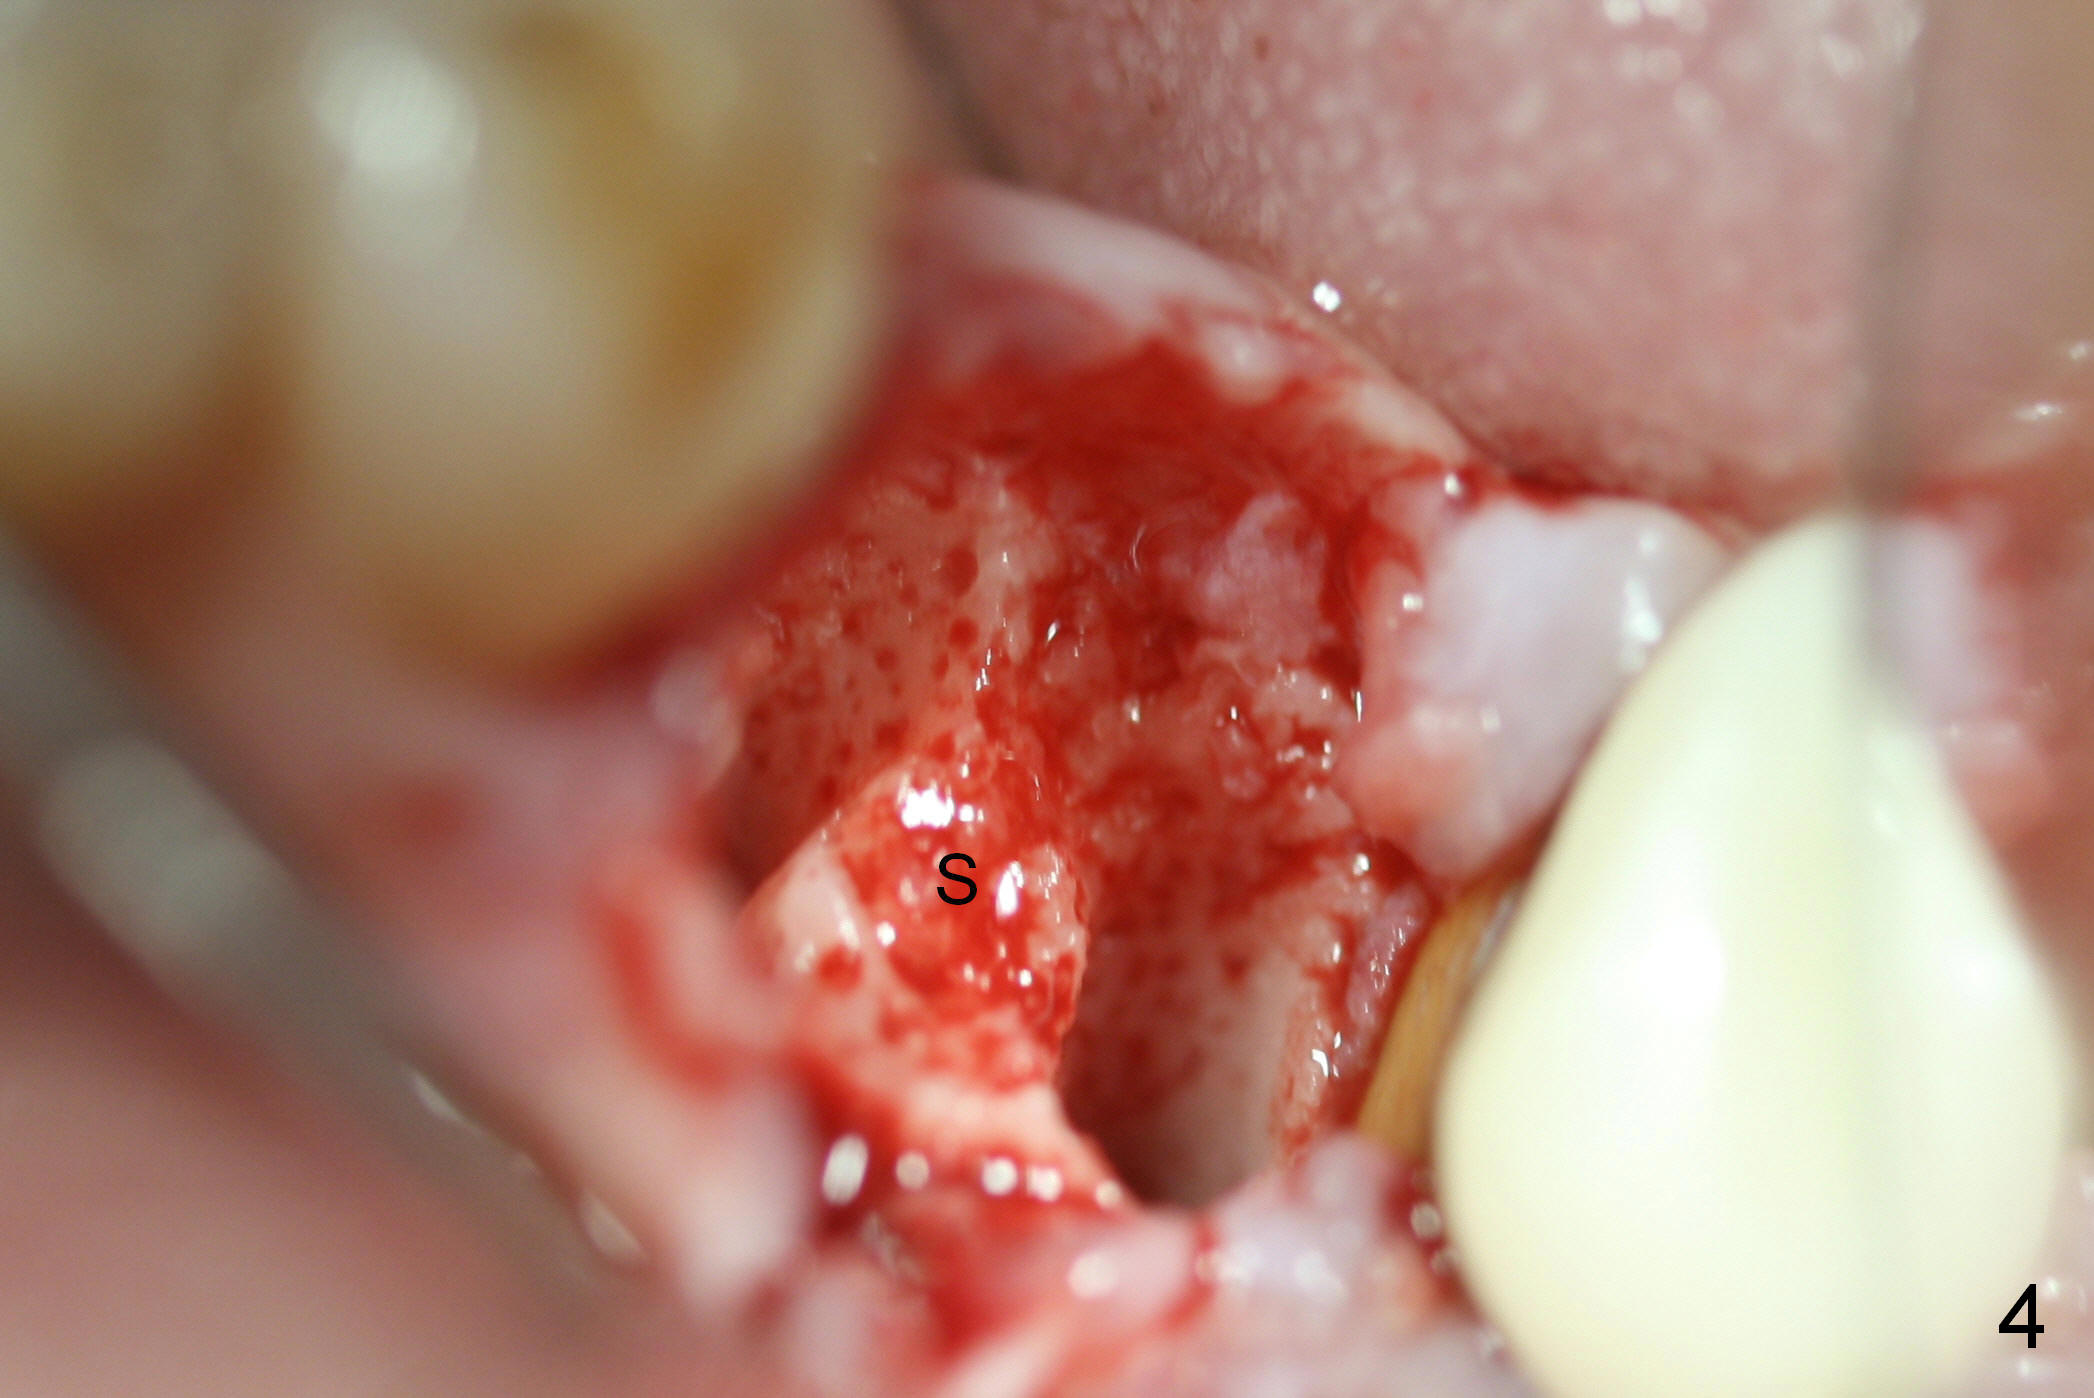

A 47-year-old lady lives out of town and presents to clinic with chief complaint "lower left back tooth easily bleeding with food impaction". Dental history and examination reveals failure of endo retreat of the tooth #19 (Fig.1), buccal gingival swelling (S), open access (A) and furcal and mesial periapical radiolucency (Fig.2 *). She is pleased to know availability of immediate implant and immediate provisional and accepts and receives the treatment at the same visit. The immediate implant (tissue-level) is designed to be as large as 7 mm and as long as 17 mm (Fig.3). To reduce paresthesia (yellow dashed line: the possible upper border of the Inferior Alveolar Canal)), a shorter implant (14 mm long in red line) is preferred. The tooth is extracted with sectioning. Granulation tissue is removed from the furca. The buccal plate appears to be intact. The septum is flat (Fig.4,10a S). Osteotomy starts in the middle of the septum with a 1.2 mm drill (Fig.10b red circle). As osteotomy increases in diameter (Fig.5 O), the apical end appears to be deviated mesiobuccally (Fig.10c large red circle). When a 6x17 mm tapered tap is being placed 14 mm deep (Fig.6 T), vibration of the buccal plate is seemingly felt at the apex (Fig.10d green circle). Further osteotomy may perforate the buccal plate. A 6x14 mm tissue-level implant is placed with >60 Ncm of insertion torque (Fig.7,8 I), followed by a 5x3 mm abutment (A) and bone graft (* in the remaining socket gap). An immediate provisional is cemented without occlusal contact (Fig.9 P).